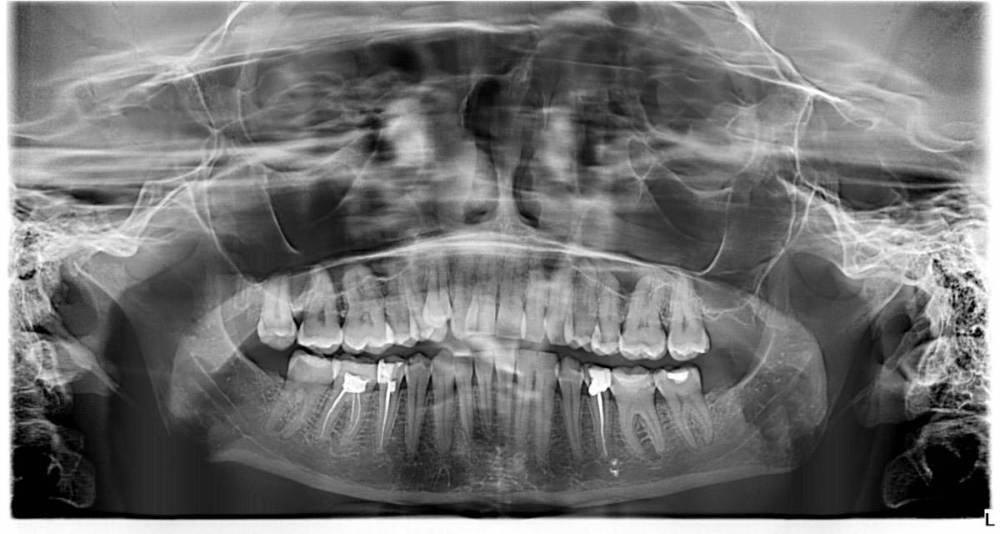

Добрый день.Обратилась к ортодонту

беспокоить начал сустав с права ,сказали заняться лечением ,удаление 8

в данный момент занимаюсь лечением зубов и сказал доктор перед брекетами ставить капу,

но сейчас чувствую что сустав не болит и не хрустит.можно ли сначало брекеты а потом капа

IMG_7742.jpeg

IMG_7741.jpeg

IMG_7740.jpeg

Ортопантомограмму (панорамный снимок)